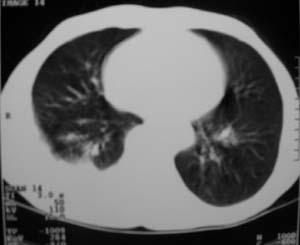

标题: CT9556:男,54岁,包裹性积液,请各位老师会诊其原因! [打印本页]

标题: CT9556:男,54岁,包裹性积液,请各位老师会诊其原因!

男,54岁,无任何不是感.体检发现右肺部阴影.现行ct进一步确诊.

包裹性积液伴胸膜钙化

右侧胸廓塌陷,肋间隙变窄,肋骨增生变粗,脏壁层胸膜肥厚、钙化。符合陈旧性结核性脓胸改变

右侧包裹性积液伴胸膜钙化.

结核性胸膜炎可能性大!脓胸!

包裹性积液伴胸膜钙化,结核性?

包裹性积液伴胸膜钙化,考虑结核性

右侧包裹性积液并胸膜钙化,性质还是结合穿刺细胞学检查的好,结核性、化脓性均会有钙化。

包裹性积液伴胸膜钙化,原因多种,国民一般为结核性居多